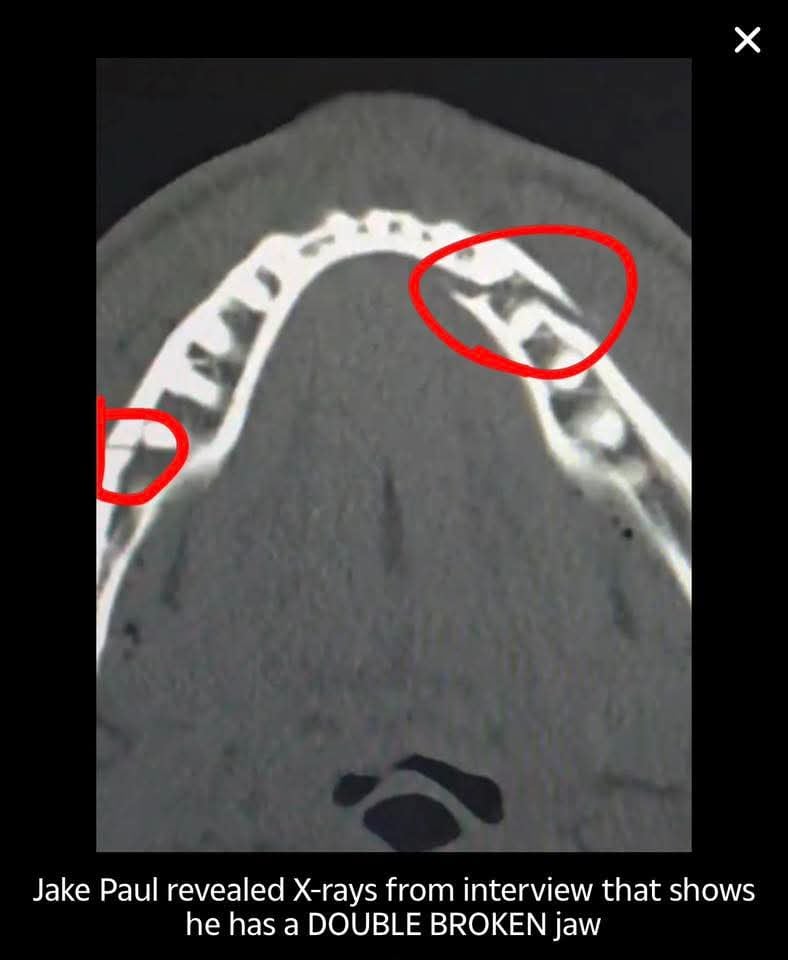

Spent half the time running or hugging AJs knees. There was a massive risk of Jake being seriously hurt and still went home with a broken jaw even after AJ took it easy on him1

Photo from jakes Instagram0 -